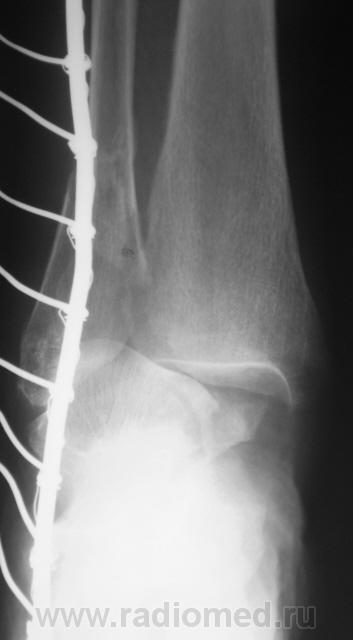

Перелом наружной и задней лодыжек. Подвывих в голеностопном суставе кнутри. Подвывих в тараннопяточном суставе. Разрыв дистального межберцового сочленения.

Переломы латеральной и медиальной лодыжек, пронационный подвывих в голеностопном суставе, латеральный подвывих в таранно-пяточном, разрыв межберцового синдесмоза.

Almo правильно задал вопрос, это касается терминологии. Про вывих стопы говорят, когда имеется вывих в г/ст суставе, а подтаранный N. Если имеется вывих в голенностопе и в подтаранном в противоположные стороны, т.е. смещается только таранная кость, говорят о вывихе таранной кости. Данный случай относится именно к последнему.